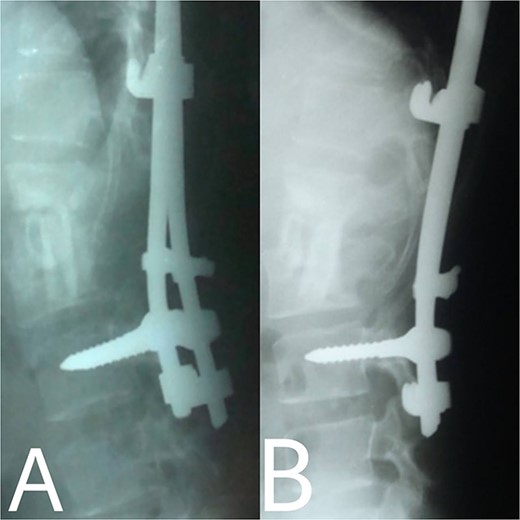

A 24-year-old farmer female was admitted to the Department of Neurosurgery with low back pain, no fever, cough, motor deficit, or any symptoms. Medical, surgical, family histories and physical examinations were unremarkable. The laboratory findings showed a white cell count of 9.8 × 103/μL, C-reactive protein concentrations of 20, erythrocyte sedimentation rate of 50 mm/1 h, 90 mm/2 h and tuberculin skin test was positive. X-ray films showed the collapse of the L1, L2 vertebrae, and L1–2 intervertebral space (Fig. 1). An abscess was observed at the L1–L2 vertebral level in lumbar magnetic resonance imaging (MRI) (Fig. 2). Chest X-rays and Sputum smear were negative. The patient was treated with anti-TB treatment (Isoniazid, Rifampicin, Ethambutol, Pyrazinamide) due to spinal TB findings on MRI (Fig. 3). After 40 days, the patient was diagnosed with grade 1/5 lower limb weakness, and bladder and bowel dysfunction, with no impairment in sensation, which predicts spinal infection. MRI confirmed these abnormalities and showed typical findings such as vertebral endplate destruction, bone marrow and disk signal abnormalities, and paravertebral or epidural abscesses (Fig. 3). Due to clinical manifestations and MRI spinal TB findings (Fig. 3), the patient underwent surgical debridement, interbody fusion and internal fixation with fibular autografting and supplemental posterior spinal stabilisation using a posterior-only approach. On post-operative follow-up, the treatment continued for 9 months, in addition to physical therapy for lower limb weakness. In the end, the patient returned to full motion with grade 5/5 in the lower limb, normal sensation, and no bladder or bowel incontinence. No recurrence was observed in the grafting area. Radiologically 2, 6 and 12 months, 14 years’ post-operation, the patient had achieved full bony graft spinal fusion (Figs 4–6).

(A, B) 2, 4 months after single-stage posterior extensive debridement and fibular autograft implantation followed by supplemental posterior instrumentation performed to treat the spinal infection.

(A, B) Complete bony incorporation between the implanted fibular autograft and host vertebral body was noted on the lateral radiograph 1, and 14 years later.